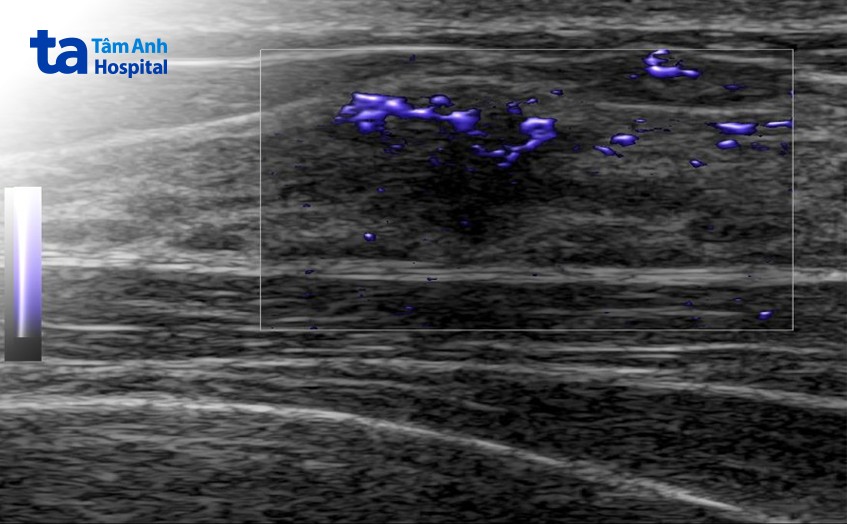

Kết quả siêu âm cho thấy khu vực sang thương ở vú phải của chị có hình thái không đều, bờ tạo gai, tăng sinh mạch máu ngoằn ngoèo, đồng thời cứng trên siêu âm đàn hồi. Để chị H. dễ hiểu về siêu âm đàn hồi, bác sĩ CKI Phạm Tấn Phát, Trung tâm Chẩn đoán hình ảnh & Điện quang can thiệp, giải thích máy siêu âm GE E10S có thể đánh giá mức độ đàn hồi của sang thương thông qua màu sắc.

Nếu khối u hiển thị màu xanh dương là cứng, còn màu xanh lá là trung tính, riêng màu vàng và đỏ là mềm. Và trường hợp của chị thì máy cho thấy vùng có màu xanh dương (cứng) bao trọn sang thương.

Với những tiến bộ của khoa học kỹ thuật, các máy siêu âm thế hệ mới hiện nay có thể giúp phát hiện những sang thương rất nhỏ, trên dưới 5mm. Ngoài hình ảnh thường quy trên siêu âm trắng đen, tín hiệu và cách phân bố mạch máu trên siêu âm doppler màu, cũng như đánh giá độ cứng trên siêu âm đàn hồi, cung cấp nhiều thông tin hơn giúp các bác sĩ siêu âm có thể đưa ra chẩn đoán chính xác hơn.